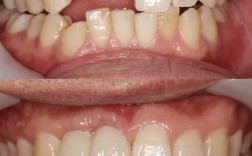

修复阶段的磨牙则针对种植牙的牙冠及咬合关系,种植体植入后3-6个月,当牙槽骨与种植体形成骨结合,即可安装基台和牙冠,此时需通过调磨确保种植牙与邻牙、对颌牙的咬合关系协调,避免早接触或创伤,医生会让患者做正中咬合、前伸及侧方运动,用咬合纸标记接触点,通过图片可清晰看到牙冠上蓝色印记的分布——若印记集中在牙尖某一点,说明存在早接触,需用高速车针精准调磨该区域,直至咬合力分布均匀,调磨后的牙冠图片会显示咬合面呈平滑的窝沟形态,与对颌牙的牙尖窝吻合,避免因咬合异常导致种植体过载松动或颞下颌关节紊乱。